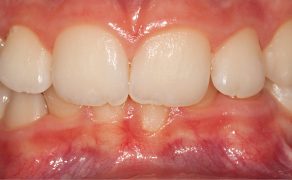

Cel. Celem pracy jest opis terapii ortodontycznej i czynnościowej pacjenta w późnym okresie uzębienia mlecznego, u którego rozpoznano: II klasę zębową i szkieletową podgrupy 2, brachycefaliczny typ wzrostu z wklęsłym profilem, ekstruzją górnych siekaczy centralnych i wychyleniem siekacza bocznego szczęki, nadmiernym napięciem mięśni żwaczy, parafunkcją zaciskania zębów i brakiem miejsca na stałe kły górne.

Opis przypadku. Artykuł opisuje leczenie 11-letniego pacjenta w późnym okresie uzębienia mlecznego, u którego rozpoznano: II klasę zębową i szkieletową podgrupy 2, brachycefaliczny typ wzrostu z wklęsłym profilem, ekstruzją górnych siekaczy centralnych i wychyleniem siekacza bocznego szczęki. W leczeniu zastosowano płytkę górną Schwarza ze śrubą trójkierunkową oraz urządzenie odciążające MFS złożone z relaksatora mięśniowego i płytki nagryzowej. Urządzenie odciążające jest efektywnym uzupełnieniem terapii ortodontycznej, wymusza długotrwałą pożądaną w terapii pracę mięśni zespołu ustno-twarzowego.